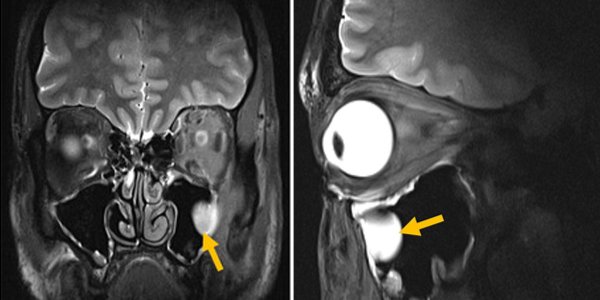

News • „Flow-void“ bei Innenohr-Bildgebung

Artefakte im Kopf-MRT: Eine Frage der Lage

Dunkle Areale im MRT? Eine Pilotstudie zeigt, dass charakteristische „Flow-void“-Artefakte im Vestibulum (Gleichgewichtsorgan) entstehen können, wenn der Patient den Kopf nicht optimal hält.